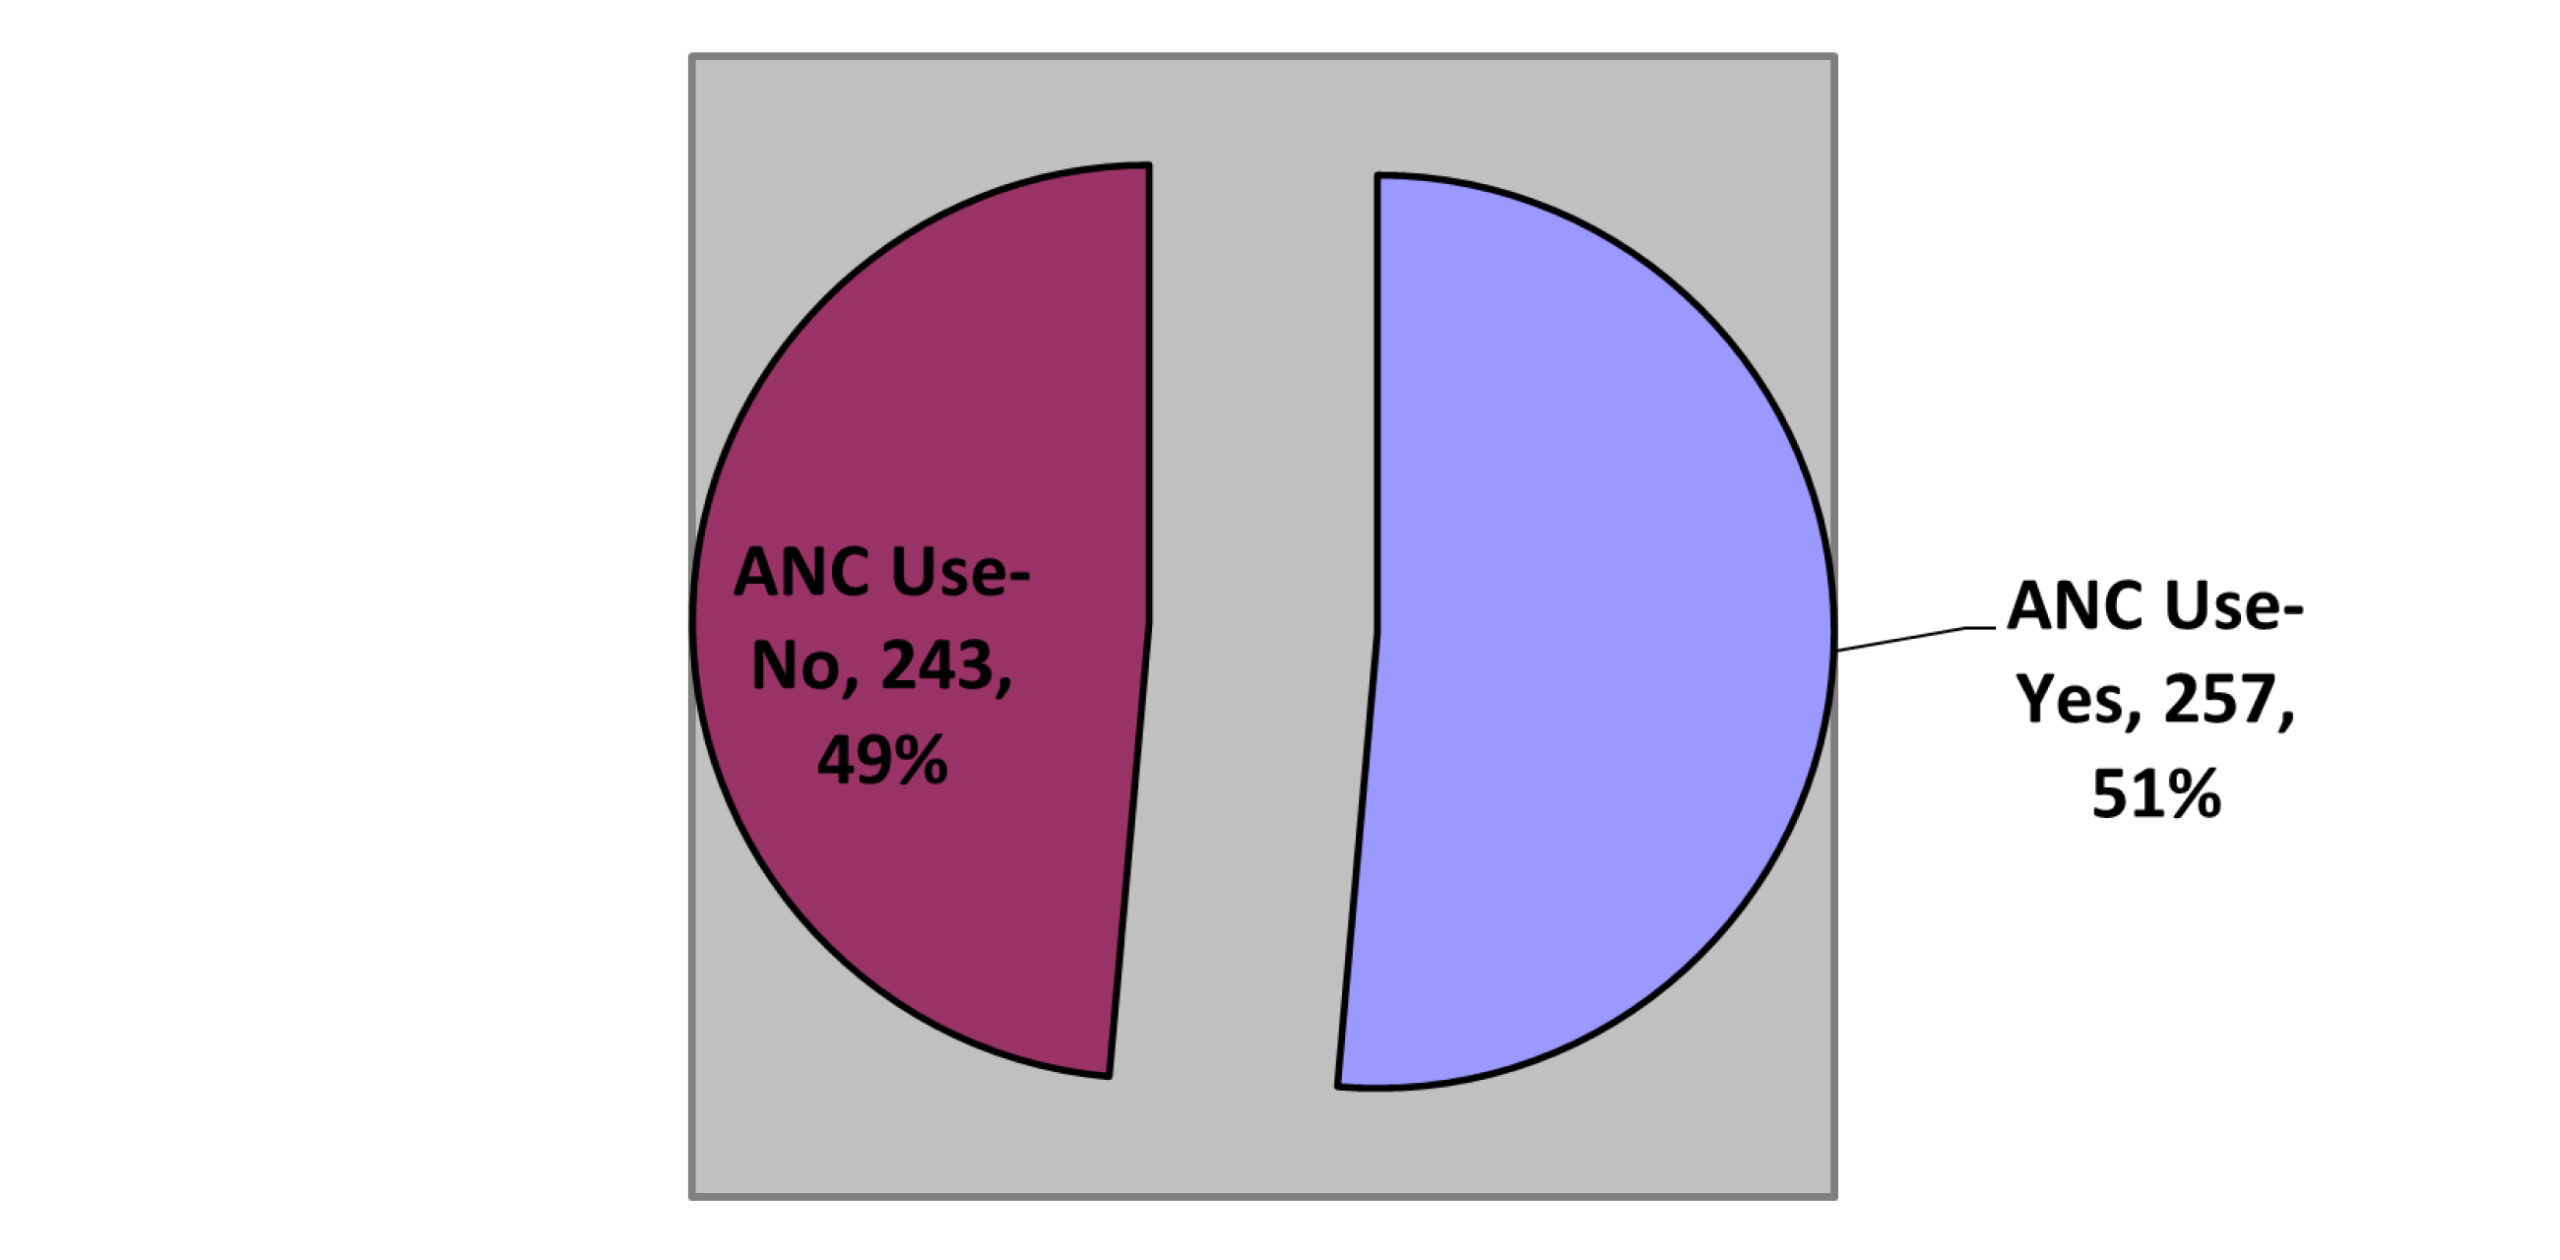

Antenatal Care Utilization and Associated Factors among Internally Displaced Reproductive Age Women in the North Shewa Camps of Amhara Region, 2023

Background: Ethnic-induced conflict has displaced millions in Ethiopia. There is a paucity of information on maternal and child health service utilization...Read More